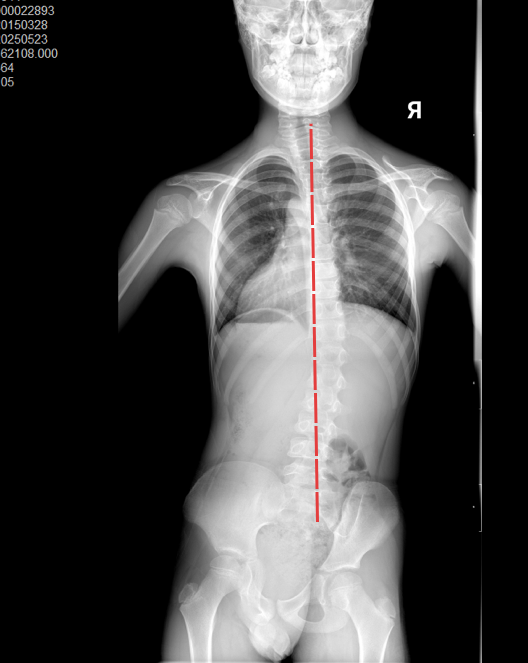

小哲全脊柱X光

脊柱侧弯明显

他立即为小哲安排了全脊柱X光和双下肢全长X光检查。影像排除了天生腿长短不一的情况后,清晰揭示了关键问题:小哲的骨盆发生了明显的旋转,连带着髋骨的位置也出现了偏移。

结合临床观察和影像资料,林主任判断小哲脊柱出现弯曲的根源,很可能是长期存在的两侧腿部力量不均衡导致的。

林主任解释了他的发现:左侧脚后跟过紧(跟腱挛缩)限制了小哲左脚向上勾脚的能力,导致走路时左脚发力不足,只能踮脚补偿。这种不平衡的走路姿势长期存在,首先引起了下半身(骨盆带)的旋转不稳定,身体为了在行走中保持平衡,脊柱最终也跟着发生了改变(继发性侧弯)。这才是造成小哲走路踮脚、肩膀不平的整体原因。